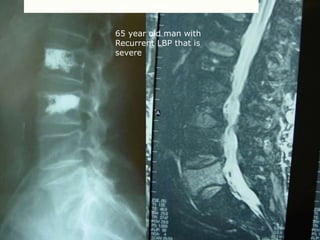

65 year old man with

Recurrent LBP that is

severe